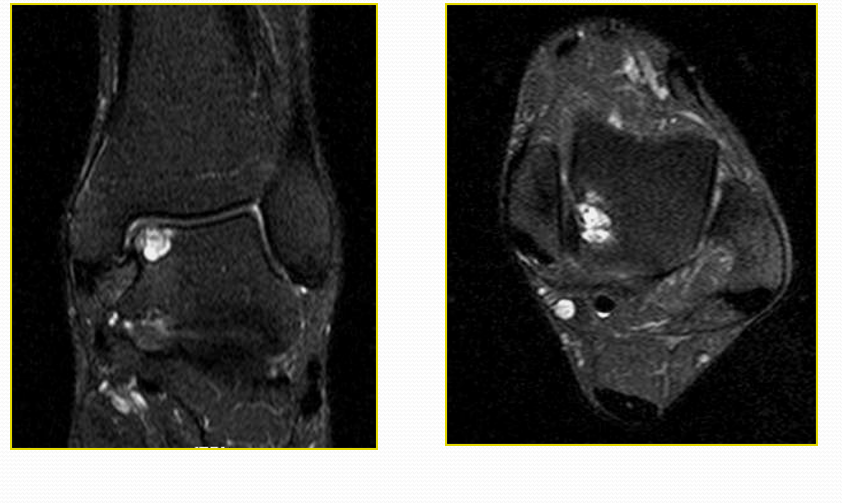

距骨骨软骨损伤

病因病理机制:

• 距骨骨软骨损伤(OLT)是经软骨的骨折、骨软骨骨折、剥离性骨软骨炎和距骨穹窿骨折的通称。

• 直接创伤或反复微创

• 骨坏死过程导致软骨下骨折和塌陷

• 累及关节软骨和软骨下骨内侧(60%)和外侧(40%)

MR表现:

MRI矢状面显示病变位于距骨圆顶最上缘,冠状面位于内侧角和外侧角。

四期:

Ⅰ期:软骨下骨小梁压缩

Ⅱ期:软骨下囊肿

Ⅲ期:不完全性碎片分离,无移位的碎片周围可见液体

Ⅳ期:碎片移位